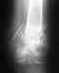

Диагноз: Неправильно консолидированный перелом левого голеностопного сустава. Наружнаяротация левой стопы.Помогите с лечением. Очень нужно.24.08.15 года травма вследствии боевых действий. Сделали надкостный остеометалосинтез вдекабре 15 года. 13.02.16 убрали шрупы, один оставили ( со слов больного). Жалобы: боль влевом голеностопном суставе при ходьбе, отечность конености, наружная ротация левойстопы, хруст в суставе, хромота.

По одним жалобам не уяснить, в чем проблема. Неизвестно, насколько хорошо был сделан остеосинтез, что там сейчас. Нужно увидеть рентгеновские снимки, хотя бы самые свежие.